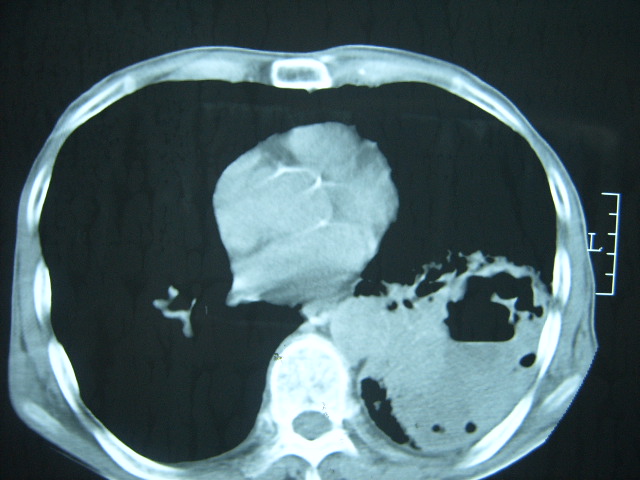

男74岁,咳嗽,寒战,低烧。有糖尿病史。

考虑:1、左下肺脓肿;

2、双肺结核。

糖尿病并发肺脓肿建议治疗后复查

考虑:糖尿病合并:1、左下肺炎继发肺脓肿;

考虑:1、左下肺脓肿;不排除霉菌感染

两肺慢性炎症伴脓肿形成,不除外继发霉菌感染。

1、左下肺肺脓肿,合并霉菌球形成?.2、双肺陈旧性病灶.3、右上肺病灶警惕瘢痕癌,建议定期复查.

两肺结核,左下肺大片实变,内见空洞性病变,壁不规则,结合糖尿病史,考虑:结核性?霉菌性?建议结合实验室检查或治疗后复查。